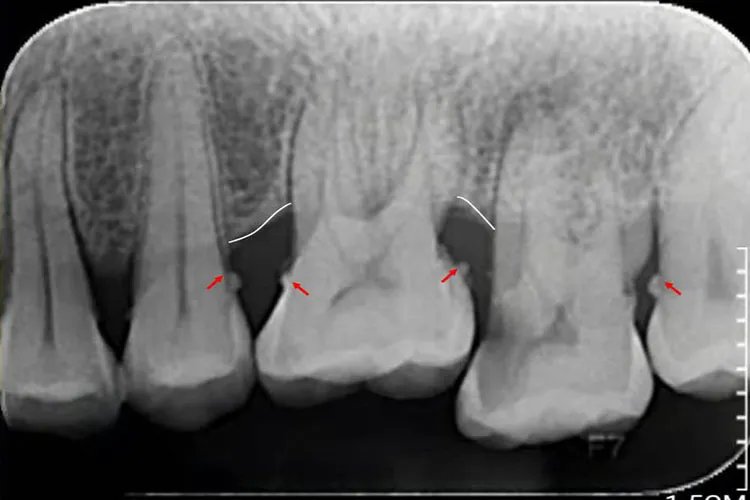

龈下牙石这种牙结石位于龈缘以下的牙面上,肉眼不可看到,可在X线上观察到,或需要探针探到。龈下牙石一般颜色较深,呈褐色或黑色,体积较小,质地较坚硬,与牙根表面的附着也较龈上牙石更牢固。龈下牙结石在任何牙位上都可形成,但以牙齿邻面和舌侧面较多。